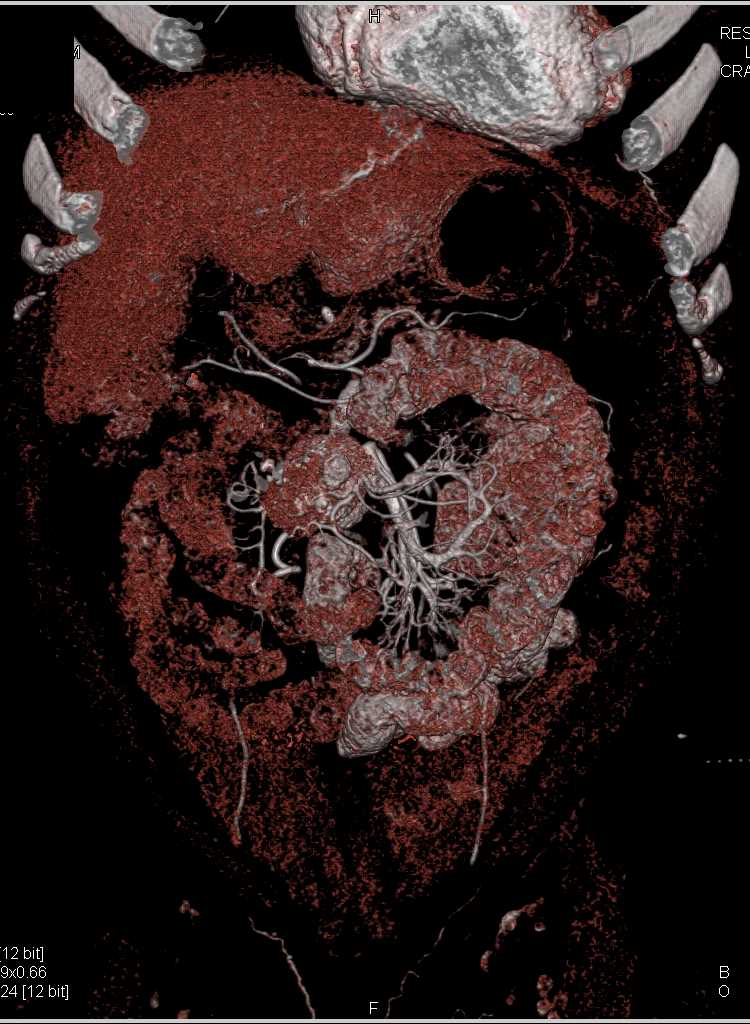

Carcinoid Tumor with Desmoplastic Reaction